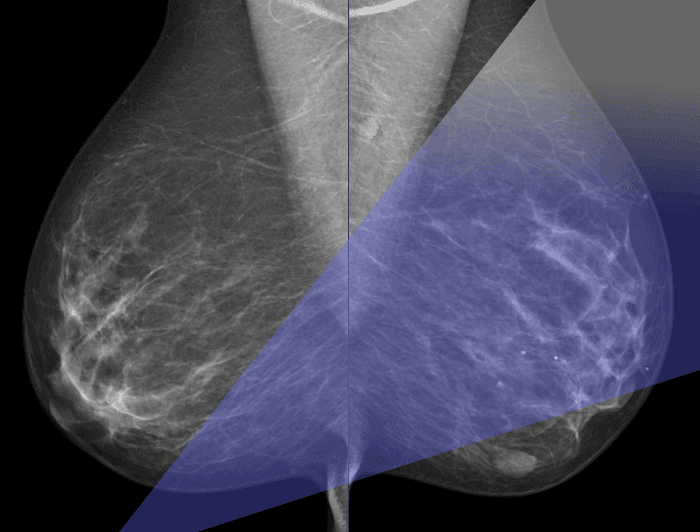

Этот интенсивный курс позволит вам получить основные знания и практические навыки в ранней диагностике рака молочной железы.

За короткое время вы сможете овладеть ключевыми навыками, которые необходимы для быстрой и точной диагностики сложных случаев. Программа курса сочетает в себе теоретические знания и практическую подготовку, что позволит вам не только расширить свой профессиональный арсенал, но и укрепить уверенность в собственных действиях.